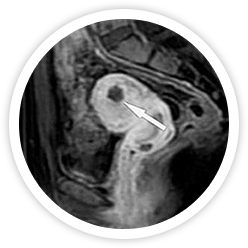

• 시술전 사진 시술 전

하이푸 시술 전에 MRI 조영증강영상에 점막하근종이 보임

• 시술 직후 시술 직후

하이푸 시술 직후 MRI 조영증강영상에 뚜렷하게 혈류가 차단된 비관류 구역을 보임

• 시술 6개월 후 시술 6개월 후

하이푸 시술 6개월 후 MRI 조영증강영상에 절제된 근종이 유의하게 축소됨

• 시술 1년 후 시술 1년 후

하이푸 시술 1년 후에 절제된 근종이 유의하게 축소됨을 보임

• 시술 2년 후 시술 2년 후

하이푸 시술 2년 후 절제된 근종은 MRI 조영증강영상에 확인 할 수 없을 만큼 완전히 흡수된